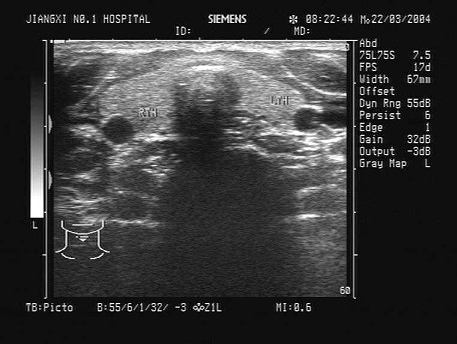

某患者脾脏声像图表现如图,诊断为()

A.正常脾脏

B.脾大

C.脾破裂

D.脾梗死

E.以上都不是